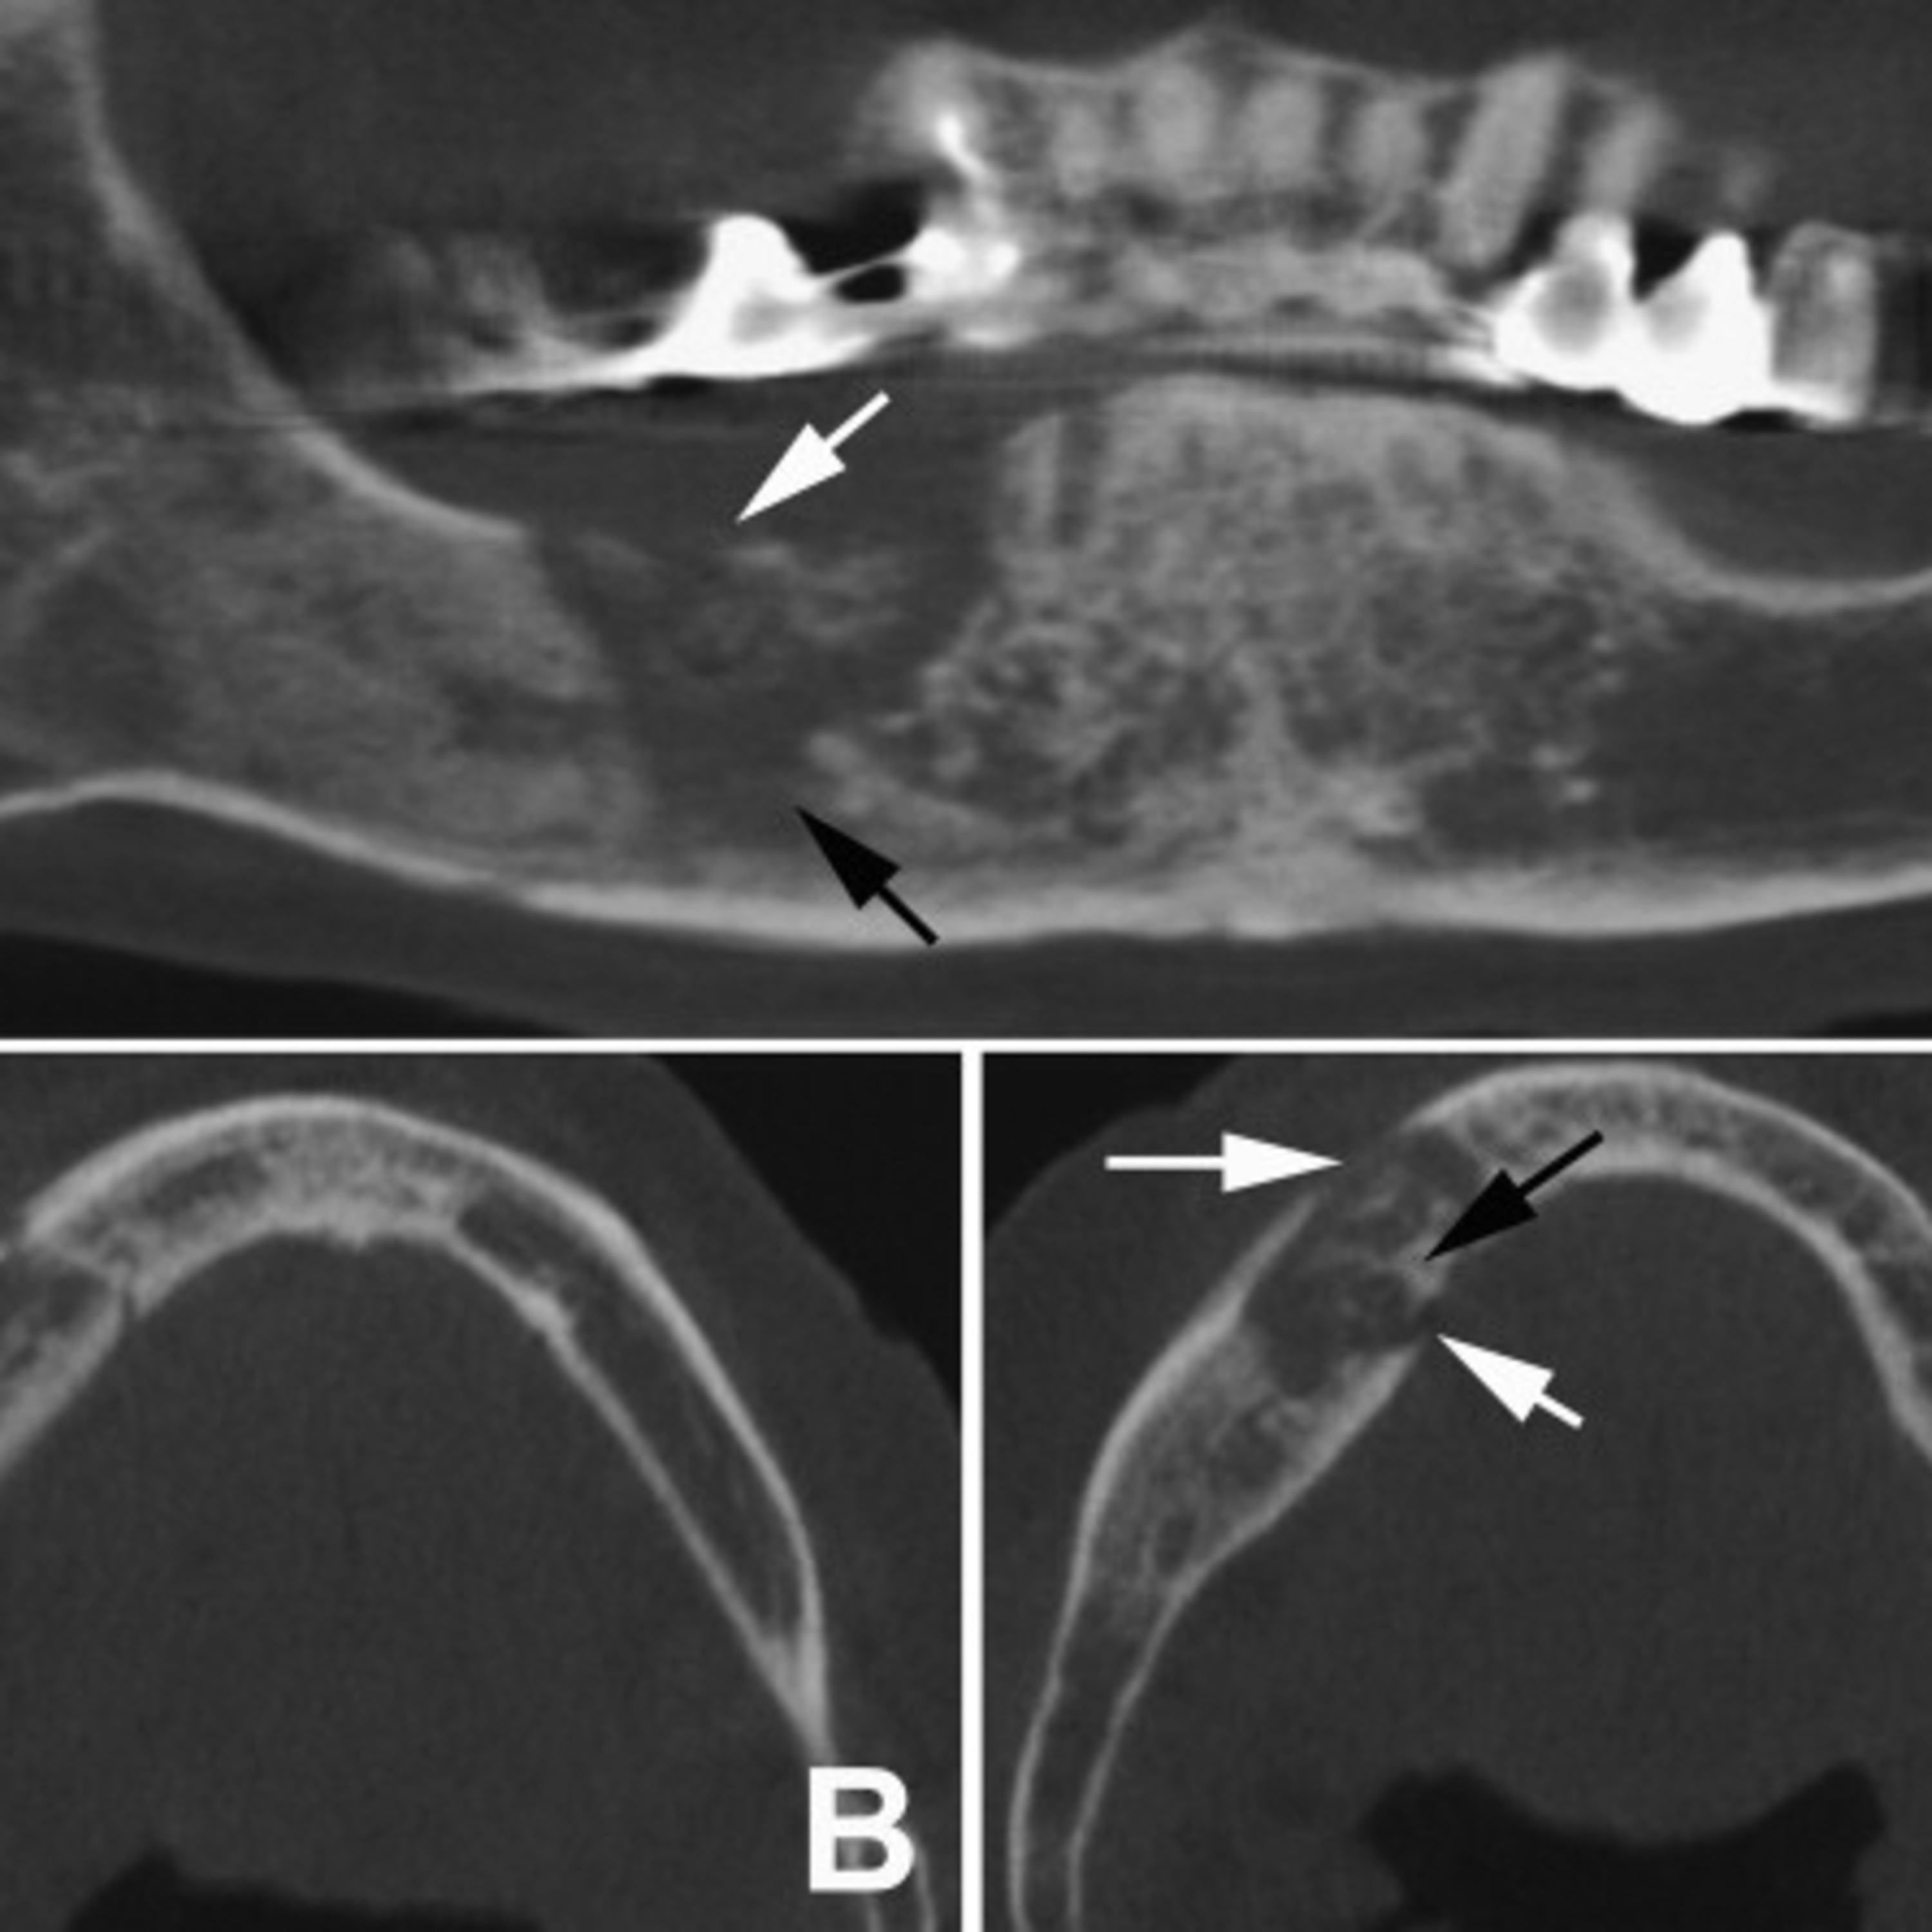

Osteomyelitis (OM) can be seen on this axial image in the right side of Why Osteomyelitis More Common In Mandible Thick cortical plates and abundant medullary tissues in the mandible contribute to confinement of the infection within bone. fistula and tooth mobility were more common in patients with chronic suppurative osteomyelitis than in those with acute disease. osteomyelitis occurs more commonly in the mandible than the maxilla, which may be related to the reduced blood supply to the. Why Osteomyelitis More Common In Mandible.